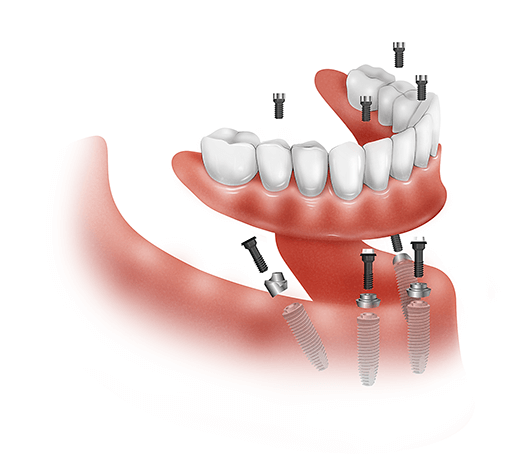

People taking certain medications, such as steroids or drugs that suppress the immune system, may not be suitable candidates. See the article : Dental Implants Plantation. And people with certain habits, like people who grind or grit their teeth hard, can put too much pressure on the implants, causing long-term damage.

The most common disadvantage of dental implant placement is that it is an expensive procedure and the service provider does not always have to be covered. Additional potential disadvantages of dental implants include: pain, swelling and bleeding due to surgery. Complications of anesthesia such as nausea, vomiting and drowsiness.

When maintained with proper hygiene and examinations, dental implants can last a lifetime. The crown attached to the implant will usually need to be replaced every 15 to 20 years, although in some cases it can take several decades.